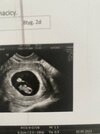

Jestem po wizycie

wszystko jest ok poza tym, ze zrobił się krwiak... termin już drugie usg wychodzi 18.12 i mówi, ze tego mam się trzymać, bo ten będzie wiodący. Wiec wychodzi, ze powinnam zdążyć na Wigilie

taka moja piękna Kruszynka

Słodkie maleństwoJestem po wizyciewszystko jest ok poza tym, ze zrobił się krwiak... termin już drugie usg wychodzi 18.12 i mówi, ze tego mam się trzymać, bo ten będzie wiodący. Wiec wychodzi, ze powinnam zdążyć na Wigilie